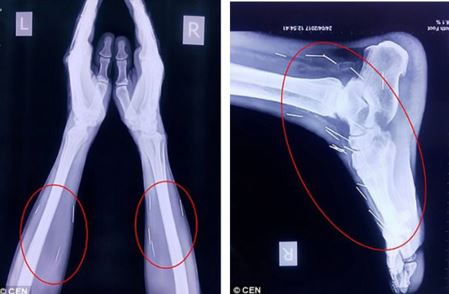

Chân và tay bệnh nhân cũng có hàng chục cây kim khác. Ảnh: DAILY MAIL

Sau khi tiếp tục kiểm tra, các bác sĩ phát hiện có tới 75 cây kim trong cơ thể ông Meena. Trong số 75 cây kim, có 40 cây nằm trong cổ họng, 25 cây ở chân và 2 cây ở cánh tay.